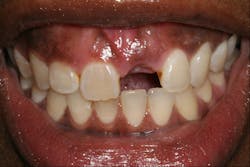

During the past 10 years, I’ve flown all over the US to mentor others in the placement of implants. The recommended compensation to the mentor is between $10,000 and $20,000 per day, funded through patient fees. Generally, the mentee nets more than $10,000 for the day as opposed to paying $10,000 to fly elsewhere for the teaching. These mentorship days are usually scheduled through an implant institute. If you are interested in being a mentor or being mentored, InstituteFaculty.com offers a detailed video explanation. The various clinical cases and figures in this article demonstrate the typical cases that would be included in a standard over-the-shoulder mentorship day. (See figures 1–6.)